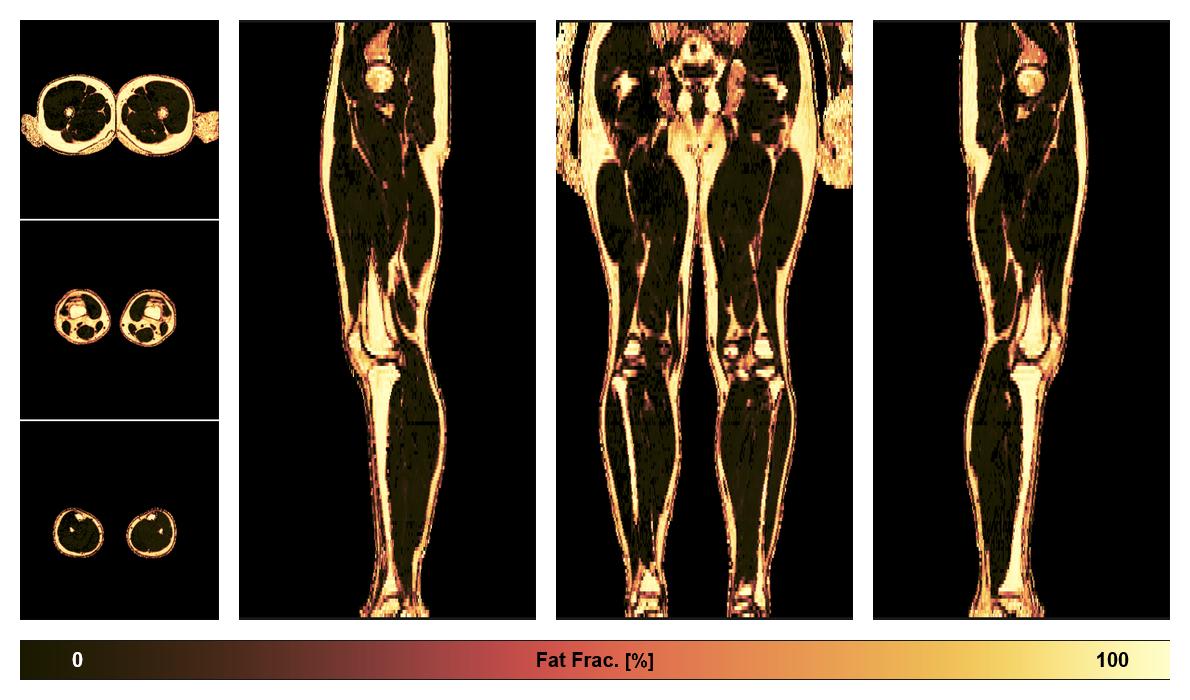

• Fat fraction

The fat fraction of the lower extremity obtained from the dixon reconstruction for muscle water fat quantification.